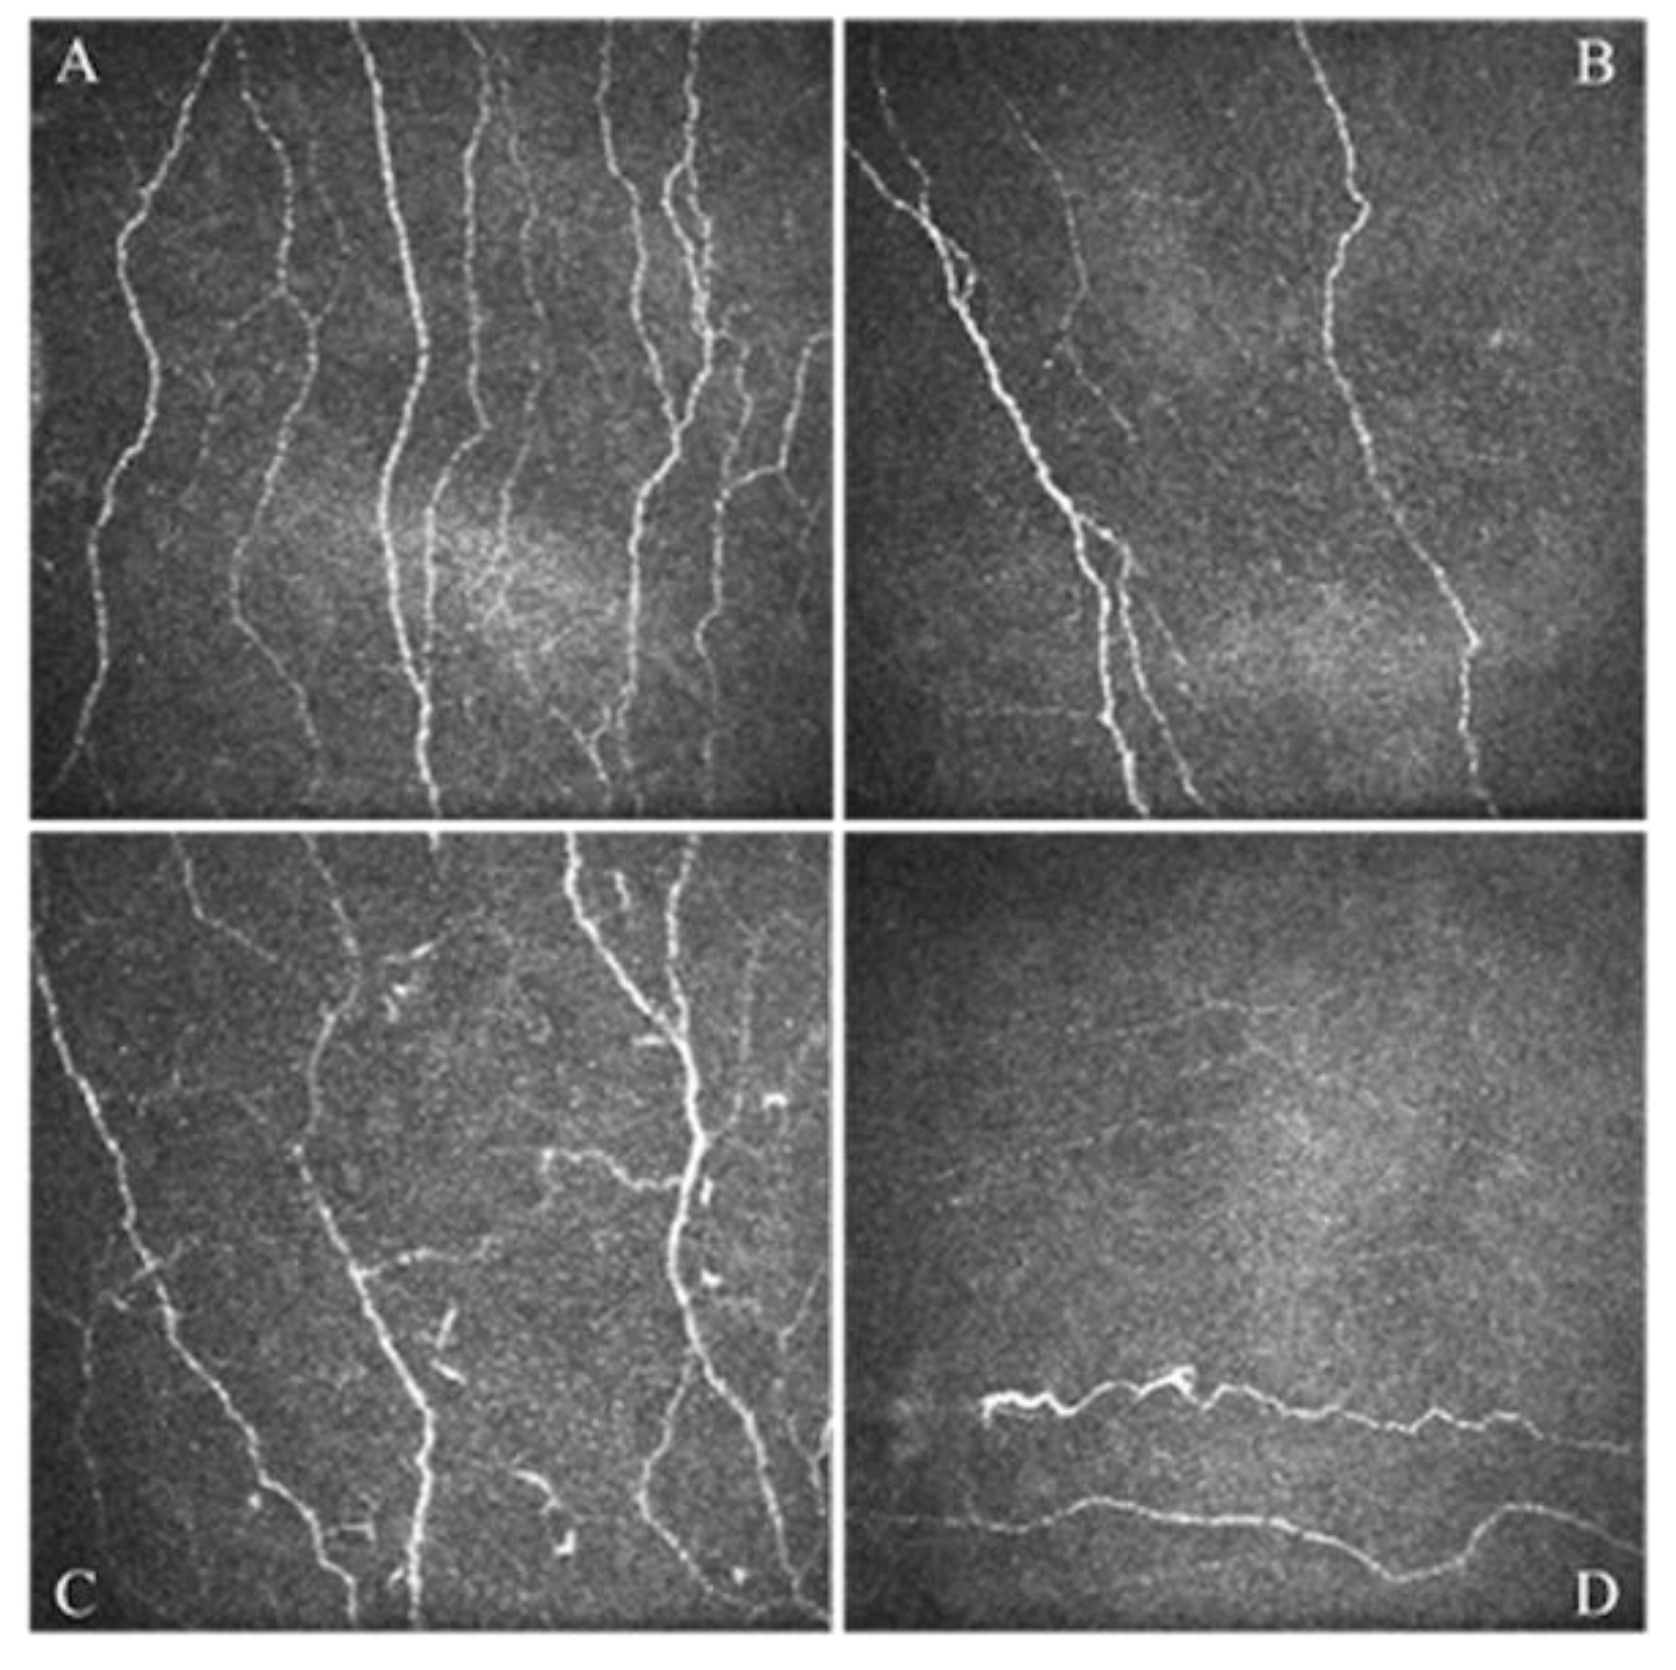

- Giannaccare, G.; Pellegrini, M.; Sebastiani, S.; Moscardelli, F.; Versura, P.; Campos, E.C. In vivo confocal microscopy morphometric analysis of corneal subbasal nerve plexus in dry eye disease using newly developed fully automated system. Graefes Arch. Clin. Exp. Ophthalmol. 2019, 257, 583–589. [Google Scholar] [CrossRef]

- Giannaccare, G.; Pellegrini, M.; Bernabei, F.; Moscardelli, F.; Buzzi, M.; Versura, P.; Campos, E.C. In Vivo Confocal Microscopy Automated Morphometric Analysis of Corneal Subbasal Nerve Plexus in Patients with Dry Eye Treated With Different Sources of Homologous Serum Eye Drops. Cornea 2019, 38, 1412–1417. [Google Scholar] [CrossRef] [PubMed]